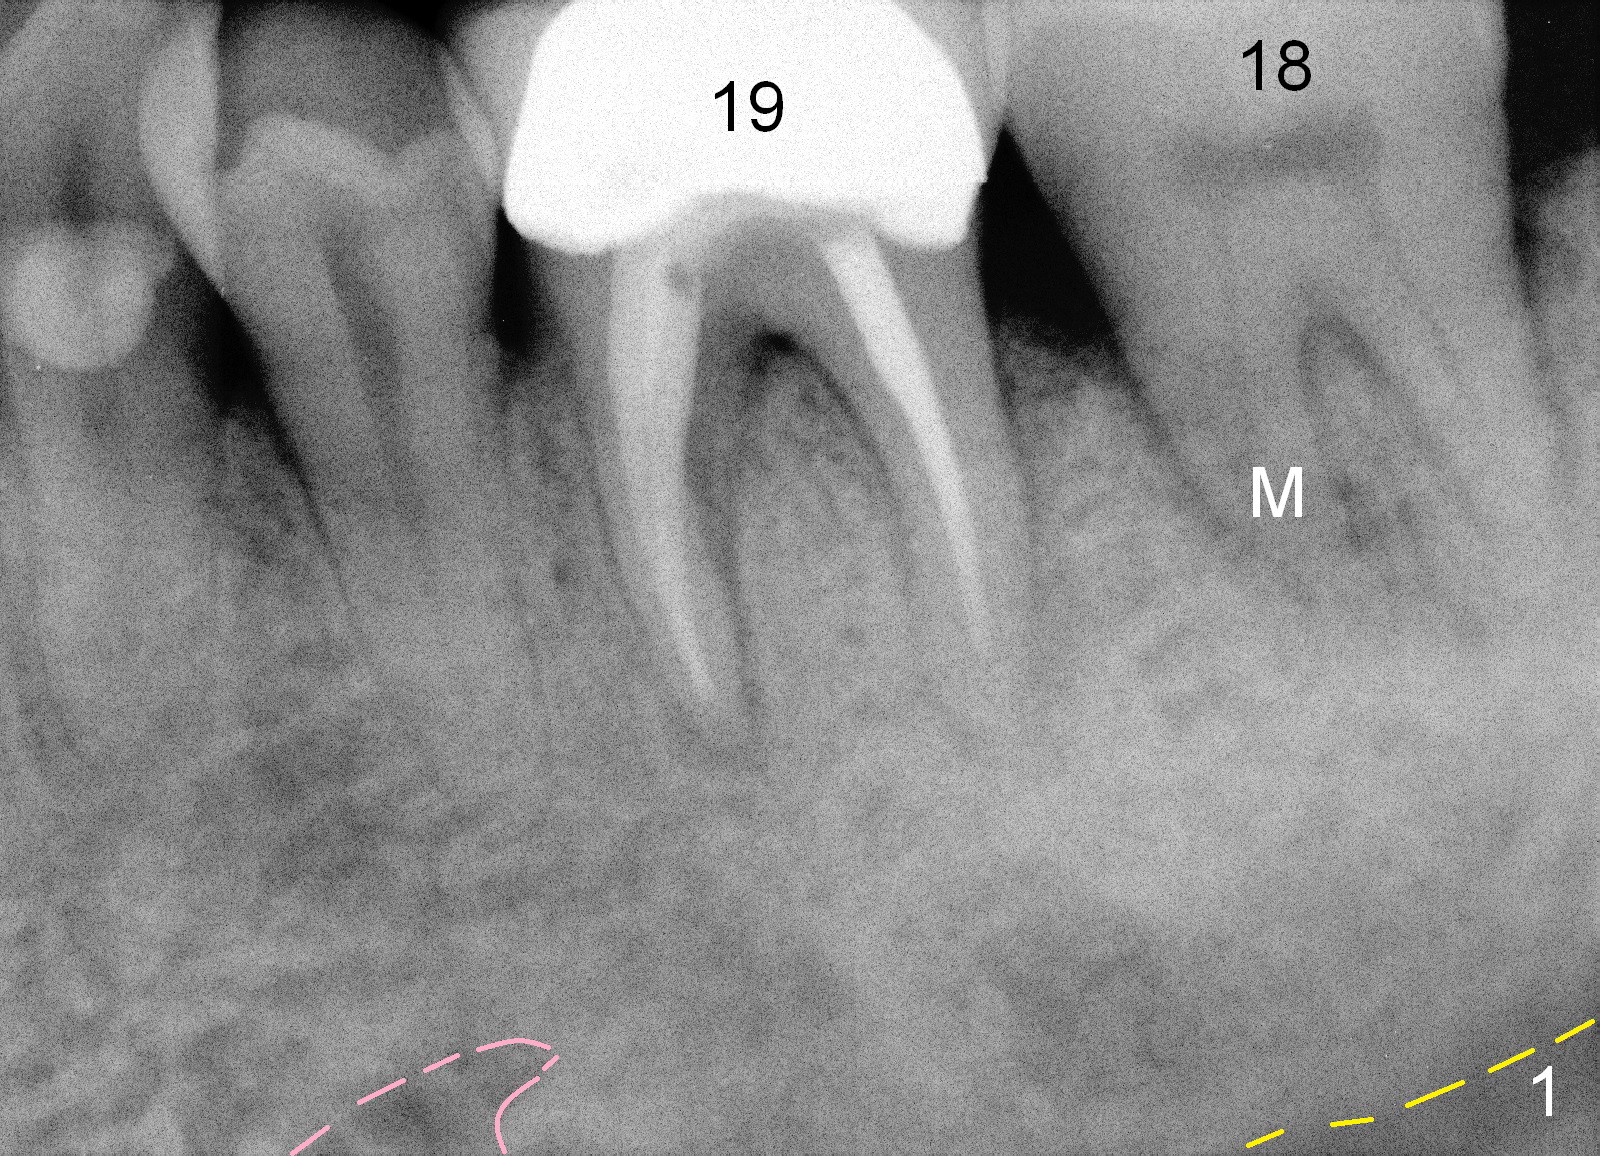

A 50-year-old man had occasional discomfort of the tooth #19 3 year ago (Fig.1). With restoration of #30 implant, the symptom disappears until now (Fig.2). He had had pain immediately before the crown of the tooth #19 was dislodged with fracture of build up. There is enlarged periapical radiolucency of the mesial root (*) with possible root fracture (arrowheads). After discussion, the patient agrees to have extraction and immediate implant.